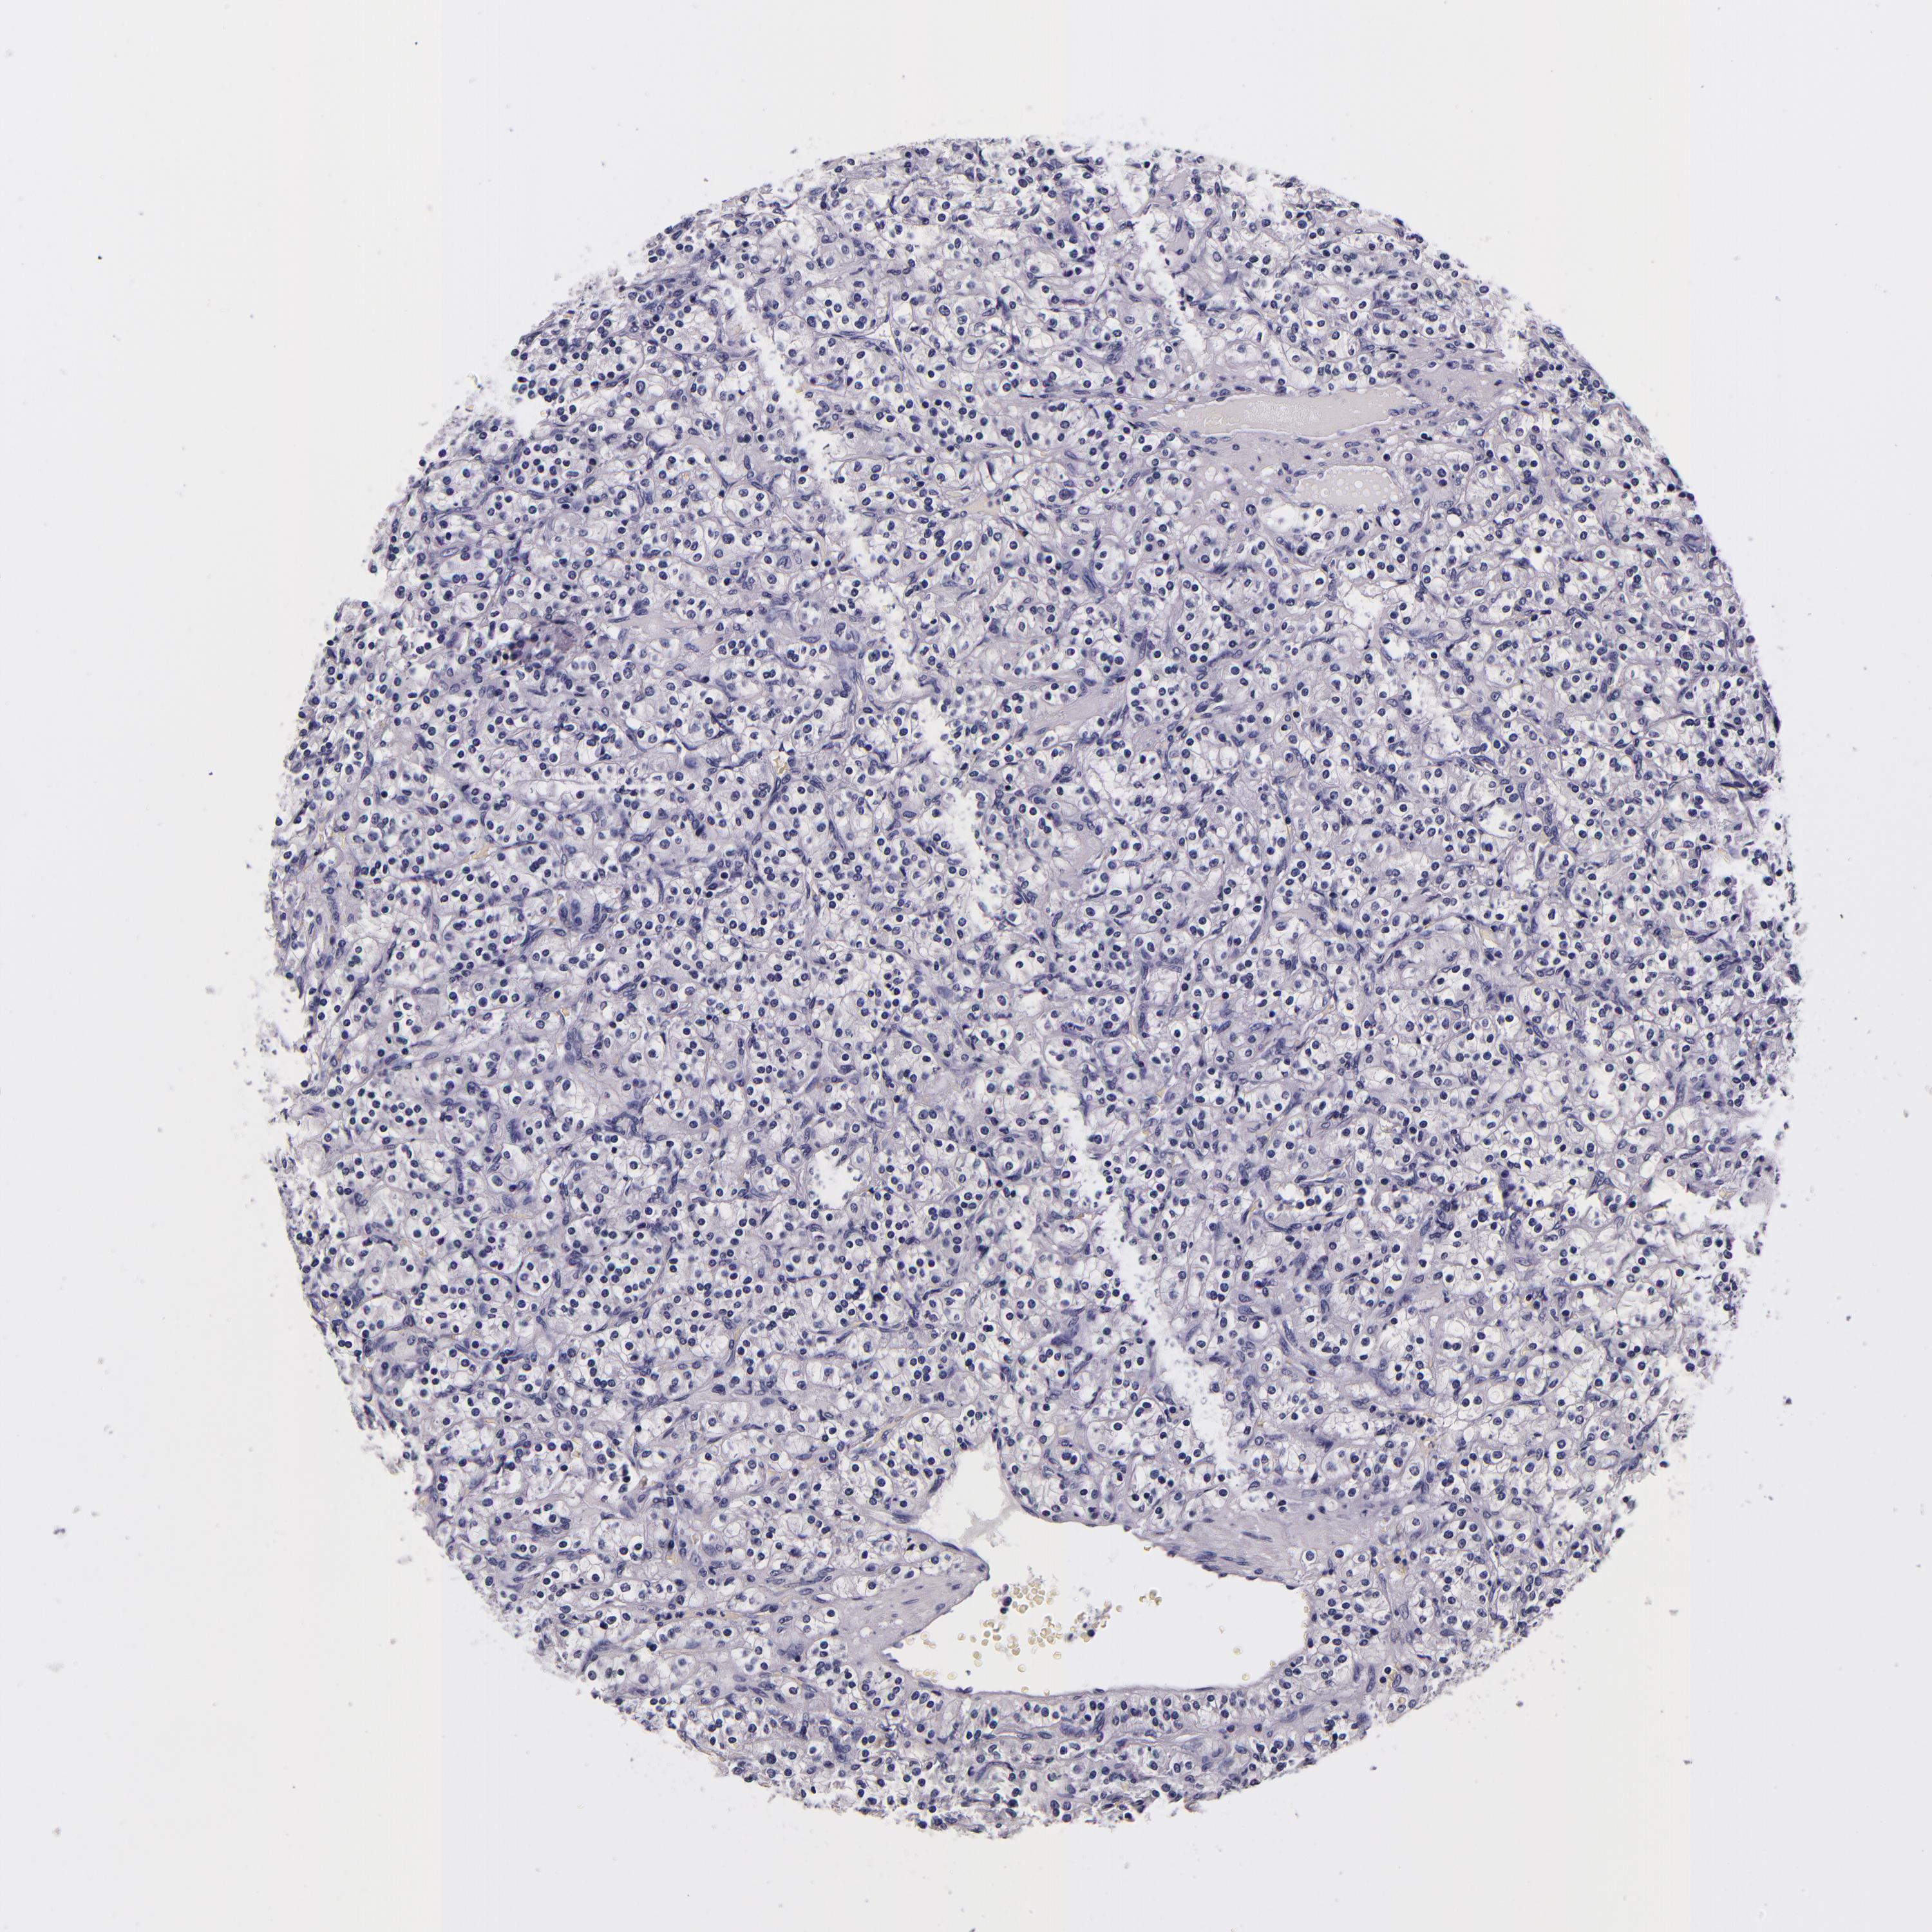

KIDNEY RENAL CLEAR CELL CARCINOMA (TCGA) - Interactive survival scatter ploti

The Survival Scatter plot shows the clinical status (i.e. dead or alive) for all individuals in the patient cohort, based on the same data that underlies the corresponding Kaplan-Meier plots. Patients that are alive at last time for follow-up are shown in blue and patients who have died during the study are shown in red.

The x-axis shows the expression levels (FPKM) of the investigated gene in the tumor tissue at the time of diagnosis. The y-axis shows the follow-up time after diagnosis (years). Both axes are complimented with kernel density curves demonstrating the data density over the axes. The top density plot shows the expression levels (FPKM) distribution among dead (red) and alive patients (blue). The right density plot shows the data density of the survived years of dead patients with high and low expression levels respectively, stratified using the cutoff indicated by the vertical dashed line through the Survival Scatter plot. This cutoff is automatically defined based on the FPKM cutoff that minimizes the p-score. The cutoff can be changed by dragging the vertical line or by entering a cutoff value in the square labeled "Current cut-off".

Under the Survival Scatter plot the p-score landscape (black curve; left axis) is shown together with dead median separation (red curve; right axis). Dead median separation is the difference in median mRNA expression between patients who have died with high and low expression, respectively. It is calculated as follows: median FPKM expression of dead patients with high expression - median FPKM expression of dead patients with low expression. This is intended to aid the user in visually exploring custom cutoffs and the associated p-scores and dead median separation.

Individual patient data is displayed and can be filtered by clicking on one or more of the category buttons on the top of the page. Categories describing expression level and patient information include: high, low, alive, dead, female, male and tumor stages. The scale of the x-axis can be toggled between linear and log-scale by clicking on the "x log" button. Mouse-over function shows TCGA ID, patient information and mRNA expression (FPKM) for each patient.

& Survival analysisi

Kaplan-Meier plots summarize results from analysis of correlation between mRNA expression level and patient survival. Patients were divided based on level of expression into one of the two groups "low" (under cut off) or "high" (over cut off). X-axis shows time for survival (years) and y-axis shows the probability of survival, where 1.0 corresponds to 100 percent.

FBN1 is not prognostic in Kidney Renal Clear Cell Carcinoma (TCGA)

: 3.9

Average pTPM 7.0

Number of samples 521